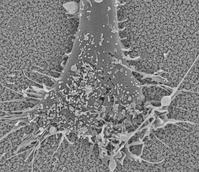

In this study, a mesoporous silica nanoparticle-based nerve growth factor delivery system has been developed and evaluated for efficacy in promoting neurite extension and growth. Such a site-specific drug delivery in the vicinity of a biomedical implant would enhance the performance of the incorporated drugs and also reduce the systemic exposure of those drugs, likely reducing or preventing toxicity and other unwanted side effects. The possible therapeutic applications of such a methodology could consequently result in the development of brain-controlled devices, vision implants, nerve function modulators, and spinal cord stimulators, to name a few future possibilities.